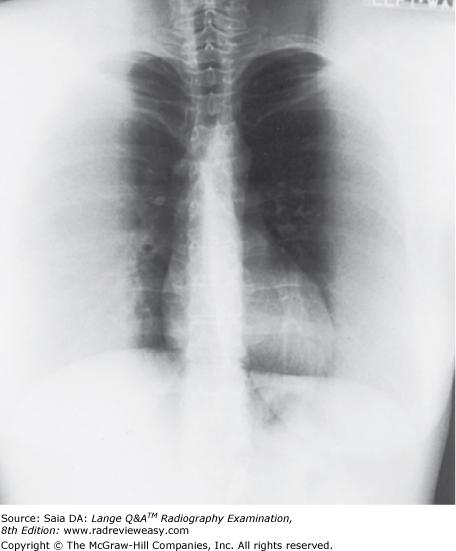

Both radiographic images shown in the figure below were made of the same subject using identical exposure factors. Which of the following statements correctly describe(s) these images?

- Image A demonstrates less receptor exposure because a shorter SID was used.

- Image A demonstrates more receptor exposure because the subject was turned PA.

- Image B demonstrates more receptor exposure because a shorter SID was used.

A 1 only

B 2 only

C 3 only

D 1 and 2 only

-In the figure, image B is darker and, therefore, has greater receptor exposure. Receptor exposure is largely determined by milliampere-seconds, SID, and exposure rate. In this case, there is a difference in SID between the two images. As SID decreases, exposure rate increases and receptor exposure increases. Image B is darker (demonstrates greater receptor exposure) than image A because image B was exposed at a shorter SID (and, therefore, a higher exposure rate).